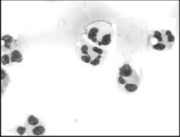

Os neutrófilos são células arredondadas com cerca de 7 micra de diâmetro e facilmente reconhecidos no esfregaço de sangue periférico (Figura 4) pela forma de seu núcleo, motivo pelo qual recebeu a designação inexata de polinucleares, quando na verdade trata-se de um único núcleo com várias zonas estreitadas, formando pontes de substância nuclear. O citoplasma ligeiramente acidófilo é repleto de grânulos heterogêneos. Os maiores são chamados de primários ou grânulos azurófilos, são peroxidase positivos, enquanto que os menores, denominados de grânulos secundários ou grânulos específicos são peroxidase negativos. São células de vida curta, seis a oito horas apenas, ligadas primariamente à defesa contra infecção e injúria tecidual. Devido a esta propriedade, os neutrófilos necessitam se mover com rapidez para alcançar o sítio da inflamação, no espaço extravascular. Para isto, expressam em sua superfície receptores para um grande número de agentes quimiotáxicos. Várias proteínas de adesão foram também identificadas nos neutrófilos, dentre elas as de particular importância, as β2-integrinas LFA-1 e Mac-1 que são ligantes para a ICAM-1 e ICAM-2.44